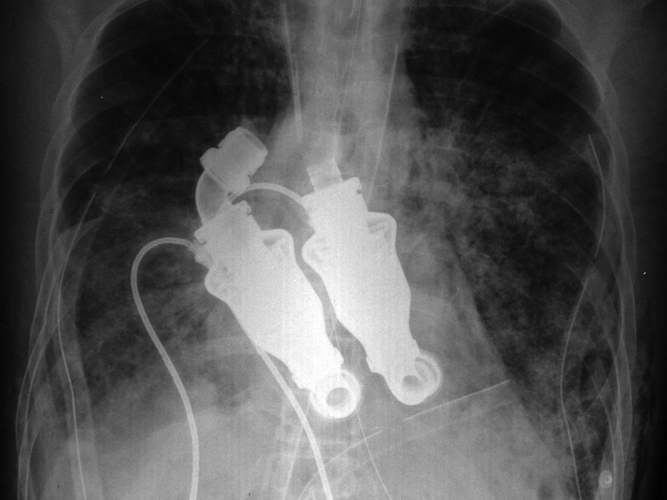

To be clear, I’m not a scientist. Or a magician. But I *think* I know scientific magic when I see it. Or, rather, hear its hum…

What I don’t understand, and can’t get from NPR’s article, is what happens to the pumps when the body dies. Like I said, not a scientist. Do they need to be removed from the corpse? If they’re controlling the blood flow but the brain is controlling body function, do they keep pumping after the brain tells the rest of the body to give it a rest? Can blood flow through the veins of a pulseless, brainwaveless body?